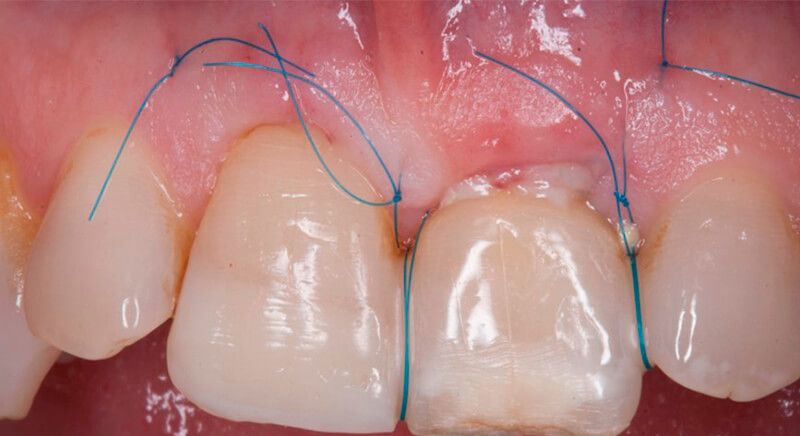

After 6 months of healing, a minimum crestal incision was made to change the 3mm abutment underneath for a 5mm abutment that would be exposed to the oral medium.

Finally, a definitive metal ceramic crown was designed and manufactured for 2.1 and a veneer for 1.1.